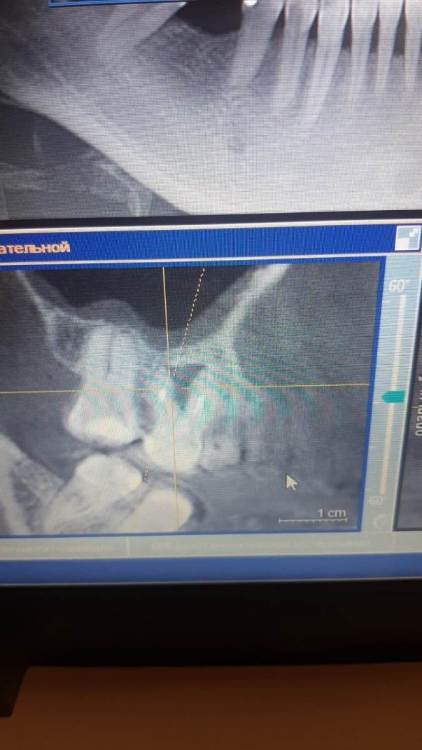

Ankauragan Опубликовано 12 декабря, 2023 Поделиться Опубликовано 12 декабря, 2023 Над 6 ой верх слева (на фото справа) - стал появляться исчезать 2 раза в этом месяце свищ, на снимке видно разрежение, можно ли вылечить или удаление?? Ссылка на комментарий

DoctorT Опубликовано 13 декабря, 2023 Поделиться Опубликовано 13 декабря, 2023 48 минут назад, Ankauragan сказал: Это я тоже прочла) про отток , Можно не удалять зуб? Видно по снимку разряжение это фатальное или попробовать лечить? мой совет - удалять. Состояние самого зуба (изменен в цвете , на 90% выполнен пломбой, разряжение в области расхождения корней, скорее всего есть подвижность) весьма плачевное. 2 Ссылка на комментарий

Ankauragan Опубликовано 13 декабря, 2023 Автор Поделиться Опубликовано 13 декабря, 2023 В моём случае возможна одномоментная имплантация при удалении? или сначала удалить, чтобы зажила? Потребуется ли наращивание костной ткани? Ссылка на комментарий

red_butler Опубликовано 13 декабря, 2023 Поделиться Опубликовано 13 декабря, 2023 1 час назад, Ankauragan сказал: В моём случае возможна одномоментная имплантация при удалении? или сначала удалить, чтобы зажила? Потребуется ли наращивание костной ткани? отсроченная 2 Ссылка на комментарий